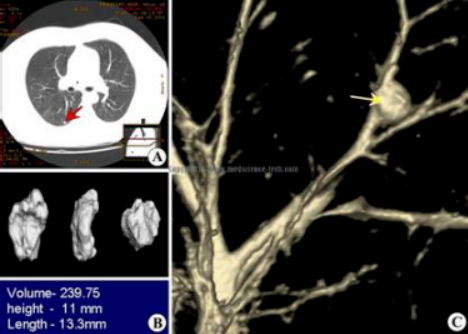

拍CT查出了7mm昁结节